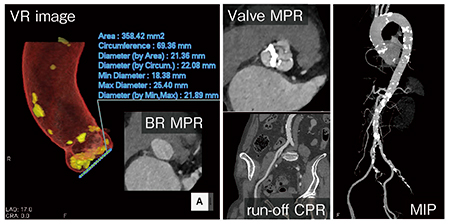

80歳代,女性。TAVI術前精査であるが,腎機能(eGFR)が27.7mL/min/1.73m2と高度に低下しており,造影剤量を低減しつつ,大動脈弁とアクセスルートの評価が求められた。

TAVI低造影剤プロトコールでは,撮影タイミングのみならず,造影剤の使用を最適化するために患者ごとの造影剤注入時間を得るためDouble-level test bolus methodを行っている。

その後,70kVのTurbo Flash Spiralにて,心位相を収縮期に合わせ,大動脈弁およびアクセスルートの画像を1回の撮影で得た。それによって,19mL(370mgI製剤)の造影剤量を達成した。

Double-level test bolus methodとは,大動脈基部と大腿動脈の2か所でtime density curveを取り,それぞれのピークとピークの間の時間を得,造影剤の注入に当たっては,それぞれのピーク時間を用いることで注入時間を患者ごとに最適化し,さらにTurbo Flash Spiralなど広範囲を高速撮影するような撮影法において,ロバストな画像収集を目的とした方法論である。

実際の画像(図3)では,TAVI術前評価に十分な画像が得られており,特にMIP画像(右)では,必要な部分のみがしっかりと造影されていることがわかる。この症例では急性期造影剤腎症の発症はなかった。

図3 症例3:大動脈弁狭窄症(TAVI低造影剤プロトコール)